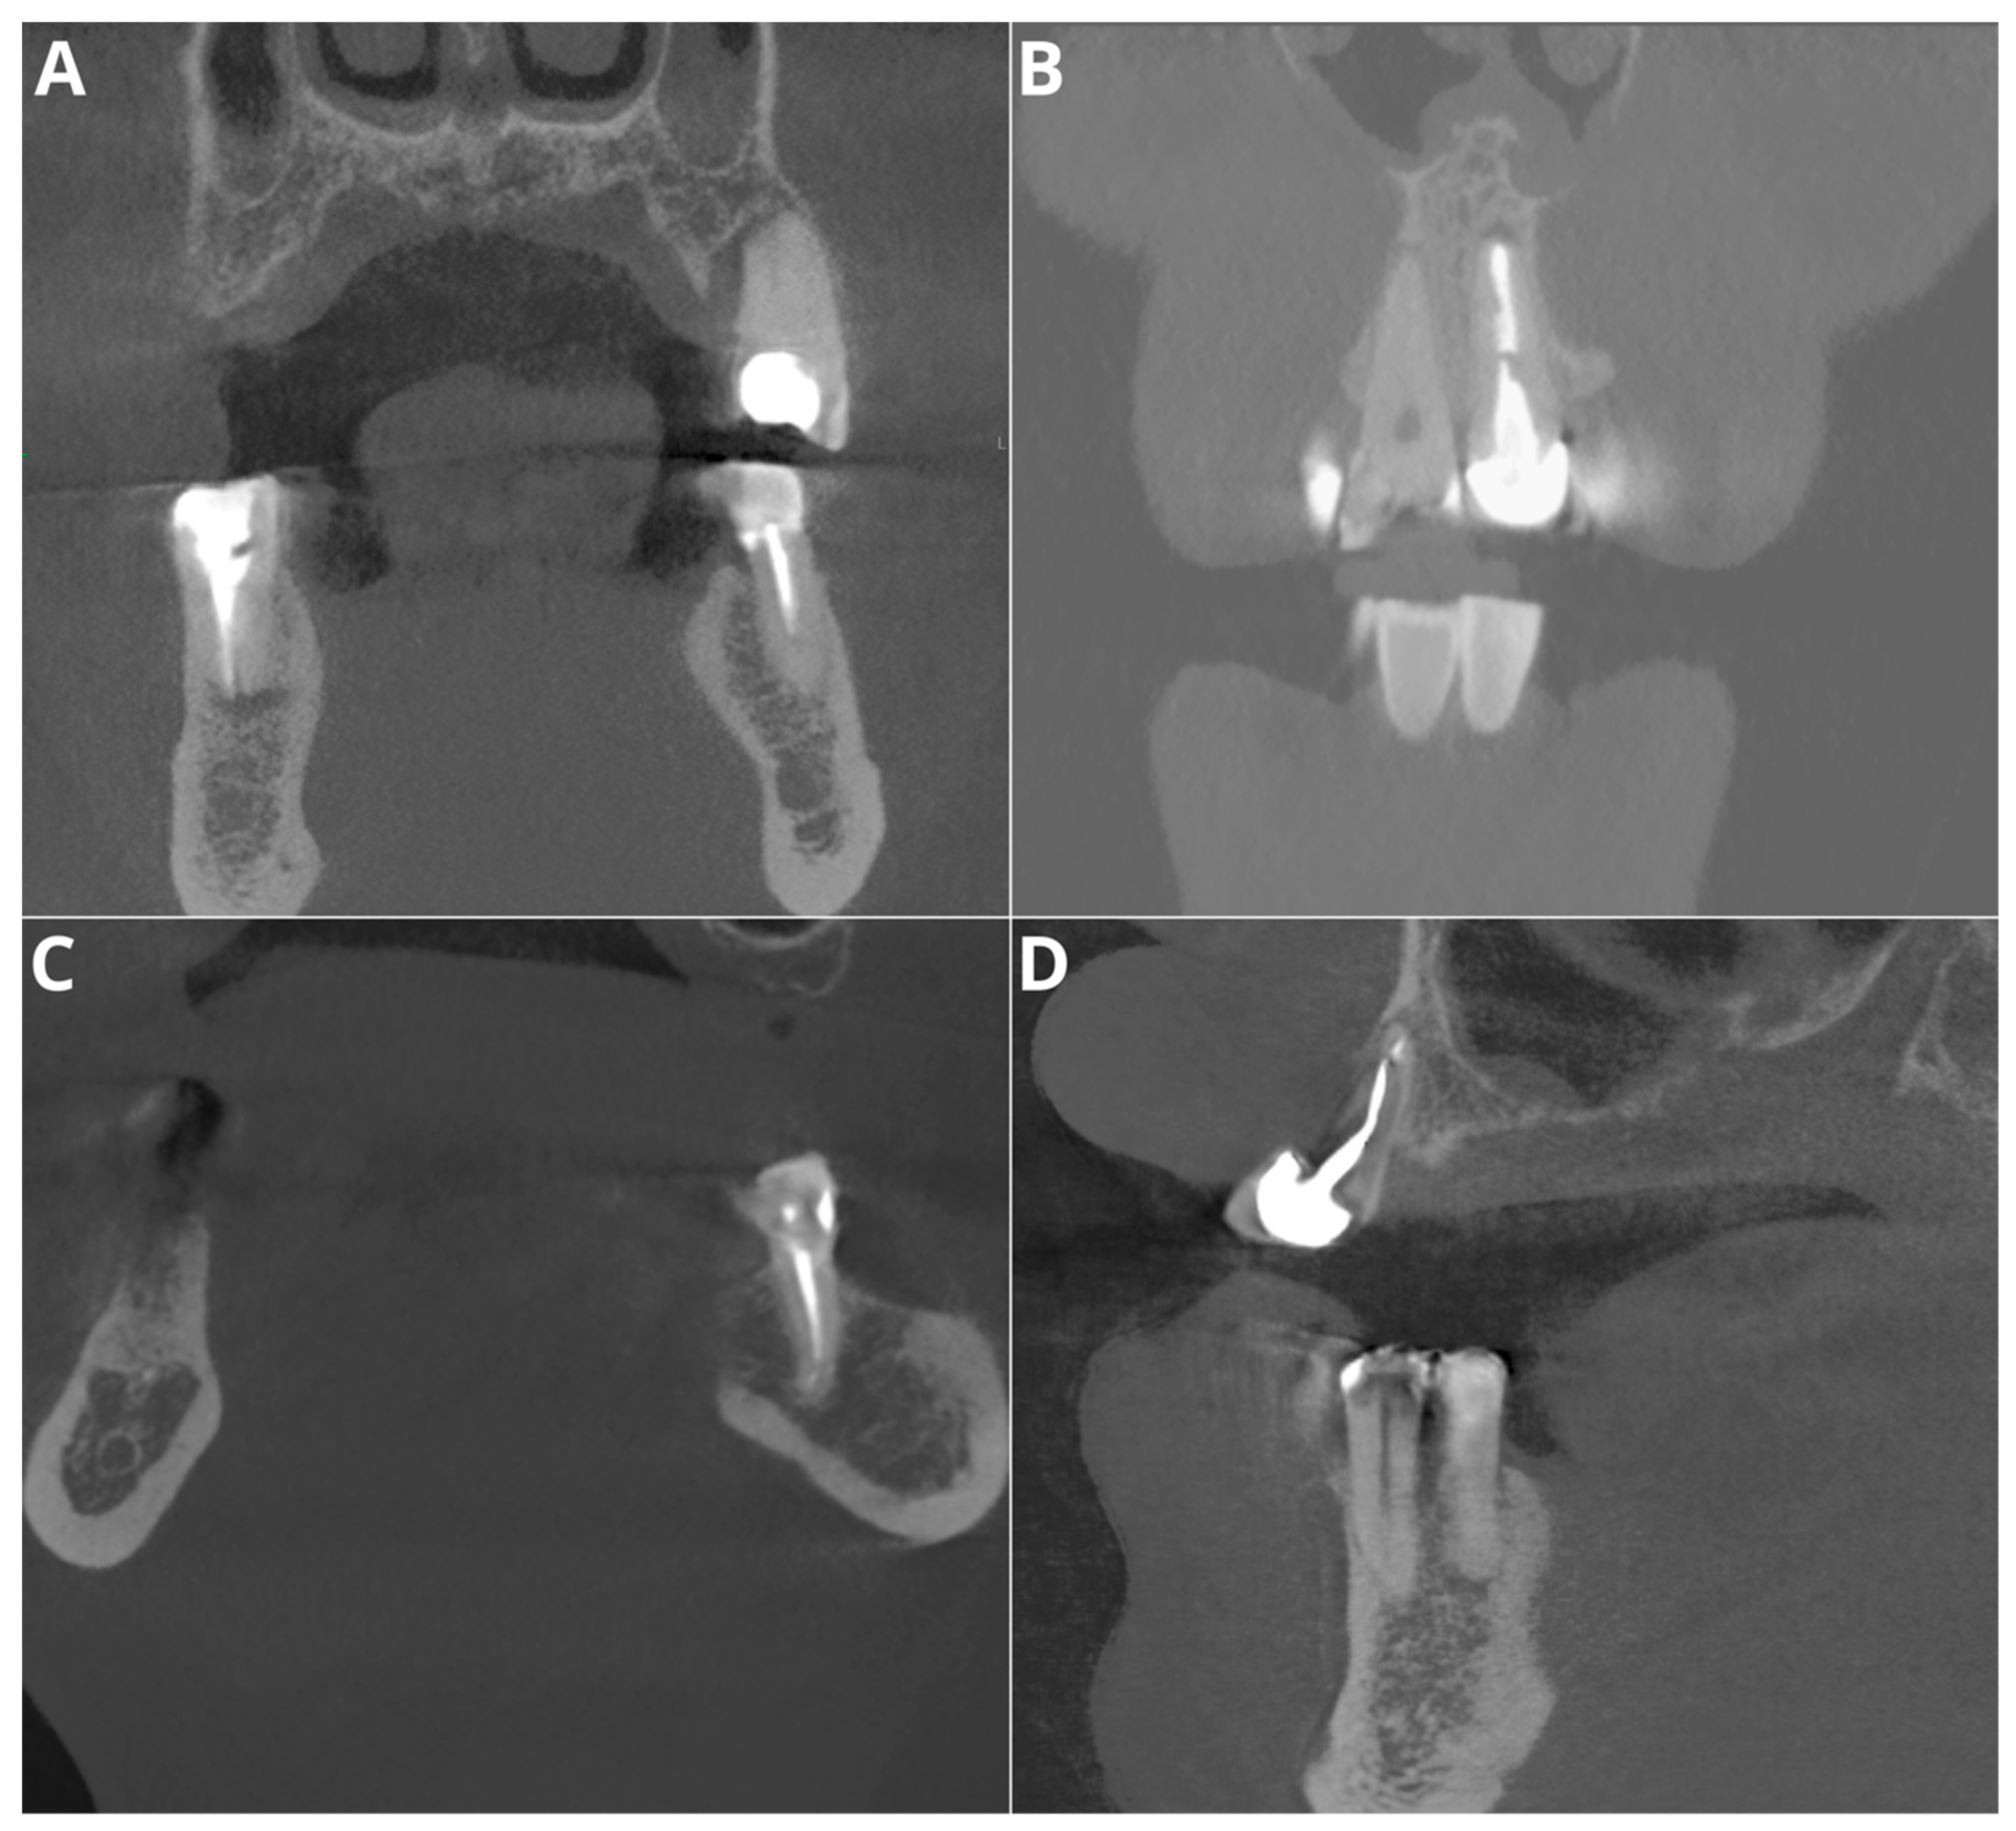

Figure 5.

Misdiagnoses in voids in filling feature assessment. (A)—tooth 35—false positive; (B)—tooth 21—false negative; (C)—tooth 34—false negative; (D)—tooth 13—false negative.